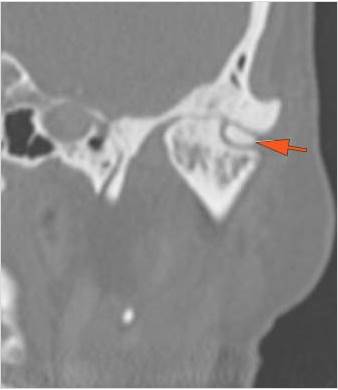

The condylar head and fossa as well as the temporomandibular joint space are fractured and/or dislocated. [Yes/No]

There is condylar fracture either within or outside of the joint capsule, or with or without involvement of the articular surface of the condylar head. [Yes/No]

There is evidence of radiodense intra-articular osteochondral fragments. [Yes/No]